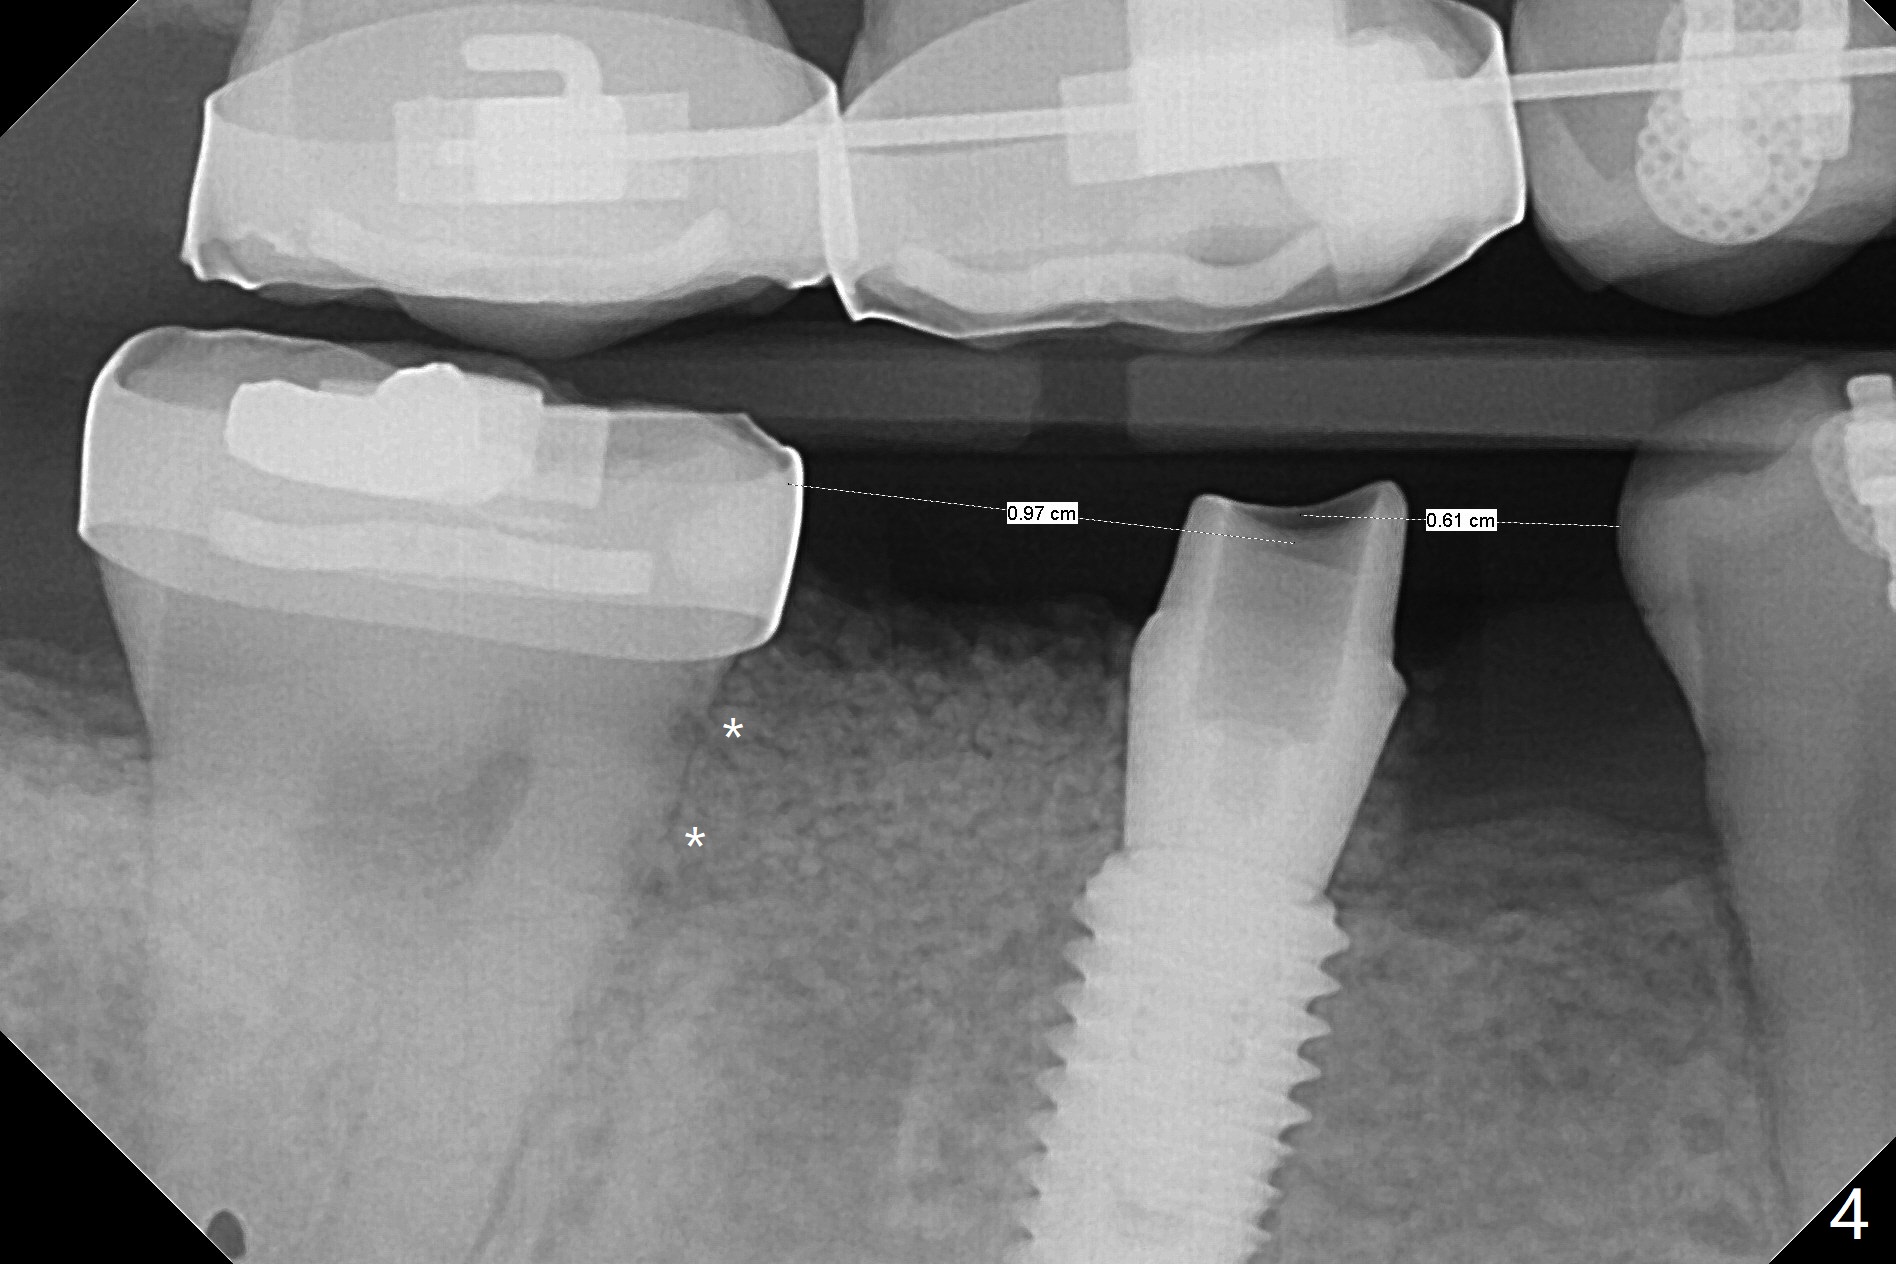

35岁男牙齿矫正后2年5个月右下6远中深龋,拔除后,近中根尖肉芽组织(图零(术前CT冠状切面):*)刮除疼痛,必须阻滞麻醉才能控制疼痛,可能与下牙槽神经分支(图零:红箭头)有关。原先准备在近中牙槽窝近中种植(5x11.5mm),术中发现近中牙槽窝种植好像方便,位置不错,不由自主在那里开始钻洞,由于牙槽窝深,钻洞必须13毫米(图一(接近神经:红虚线)),之后发现钻洞(图二(术前CT3D长轴切面(黑色:近中,远中牙槽窝)):红圆圈)不够理想,使用Lindamann Bur将钻洞往颊侧近中移动(图二:箭头),最终在这方面结果可以(图三,三’,四),虽然接近神经,术后没有神经麻痹。放置粘性骨粉(图四:*),PRF膜,4-0 PGA缝线(图五),最后使用树脂敷料(图六:A)。后牙垂直空间少,术后一周需要降低树脂敷料高度(图七)。术后一个月取出敷料,牙槽窝愈合,植体平台远中稍微暴露(图八),准备一个月后制作临时牙冠。术后两个月植体远中没有暴露,但是基台远中边缘太高了(图九:>),换成6x4毫米愈合基台。下个月换成袖短的修复性基台,安置临时牙冠,牵拉7。舌侧cleats之间放置power chains,颊侧power hooks。其实术后4个月安置临时牙冠和band(图十),牙冠牙合面加高,这样7可以无阻挡移动(图十一:*;16x22 arch wire)。7远中放置power hook行不通,因为末端碰到颊侧前庭牙龈,造成创伤。只好用7颊侧原有牵引勾,在6近中安置一个短的power post (? 图十:箭头),按常规post往下,之间放置12毫米closed spring。如果post往上安置,7牙根牵引可能更有效?近中牵引一个月,第二磨牙前移大约2毫米(图十二:^),稍微近中倾斜,closed spring从12毫米更换到9毫米,舌侧换新的power chains x 4。下一个预约,用sensor 1拍摄根尖片证实第二磨牙近中倾斜,然后在它远中16x22钢丝安放power hook,下缘向颊侧弯曲,避免接触接触粘膜。